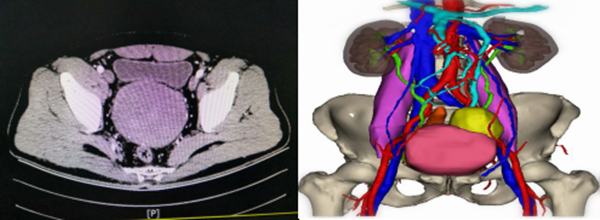

术前按流程进行3D成像后,让腹膜后肿瘤彻底现形, 13cmX9cmX8cm大小,呈现出典型的“葫芦娃”形状,头小身子大,但并未侵犯膀胱、前列腺、精囊腺、直肠、输尿管,与肠系膜动静脉、髂内动静脉之间有一定的间隙和界限,滋养血管来自于肿瘤周边的小血管,非常适合进行微创腹腔镜手术切除。术前用3D成像认真讲解肿瘤情况、与周围的关系、手术路径等后,病人和家属紧张焦虑的心情缓解了许多,思想包袱也放了下来。术前充分与患者及家属进行知情同意后,经积极完善周密的术前讨论和准备后,在麻醉科和手术室的大力协作下,2020年于9月4日上午由王志东副教授主刀,在黎跃华主治医师、侯乐医师协助下,成功实施腹腔镜微创“葫芦娃”切除术。术中探查的情况与术前3D成像预计基本相同:“葫芦娃”形状肿瘤位于腹盆腔腹膜后,13cmX9cmX8cm大小,包膜完整,与膀胱、前列腺、直肠、输尿管等盆腔脏器界限较为清楚,提起显露肿瘤与肠系膜动静脉、髂内动静脉之间有一定的间隙,肿瘤供血血管来自周边细小血管,超声刀完全可以切除凝闭血管,做到完整切除肿瘤。术中仔细分离、结扎肿瘤滋养血管,保护好生命攸关的各个血管、脏器、神经,在没有损伤周围脏器、未输血的情况下将肿瘤完整切除,腹部左下方取小切口完整取出肿瘤,手术获得成功,术中出血约100ml,手术顺利,切下来的“葫芦娃”与3D成像模型几乎完全吻合(如下图所示)。患者术后恢复良好,达到了快速康复治疗的目的,即将痊愈出院,达到了预期效果。